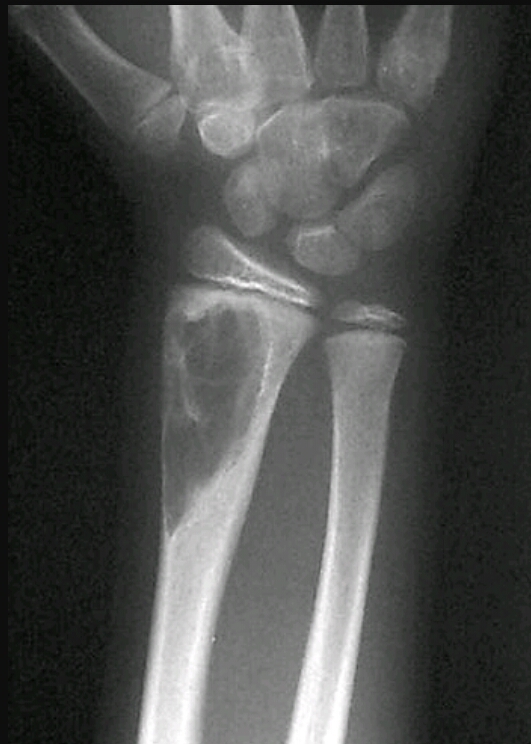

Findings? Diagnosis?

Lytic , eccentric lesion in the metaphysis, soap bubble appearance

GROWTH PLATES, NOT SUBARTICULAR

aneurysmal bone cyst